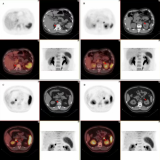

纽瑞特医疗完成68Ga-NRT6020注射液及177Lu-NRT6020注射液安全性和耐受性I期临床试验首例受试者入组

近日,由成都纽瑞特医疗科技股份有限公司(以下简称纽瑞特医疗)申办的一项评价68Ga-NRT6020注射液及177Lu-NRT6020注射液在FAP阳性晚期恶性实体瘤受试者中的安全性和耐受性的I期临床试验于复旦大学附属肿瘤医院(主要研究者:宋少莉教授、张剑教授)成功完成首例受试者给药,这标志着该项临床研究已从筹备阶段正式进入实质性实施阶段,也是68Ga-NRT6020注射液及177Lu-NRT6020注射液诊疗一体化开发过程中的一个重要里程碑。关于FAPFAP是具有细胞... 2025-12-05 核医学放射性药物核医药